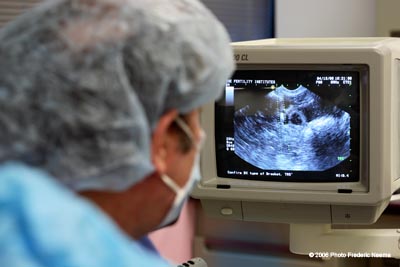

Dr. Jeffrey Steinberg looking at the monitor that helps him to guide the needle. The vertical white rectangle shining in the center of the image shows the tip of the needle as the follicular fluid is aspirated from the follicle. Dr. Steinberg, founder of the Fertility Institutes, uses Preimplantation Genetic Diagnosis (PGD) technology in conjunction with in-vitro fertilization to help couples to choose the sex of their future babies with a 99% success rate.